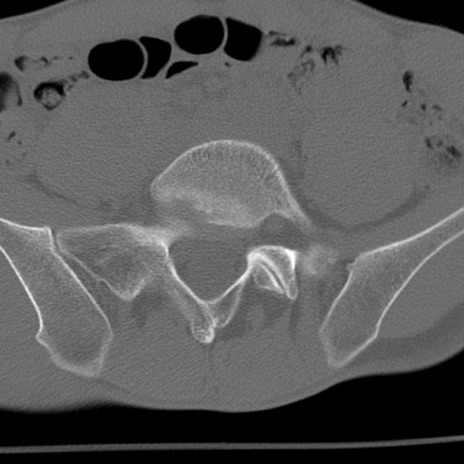

症例3 腰椎CT(横断像)

腰椎CT